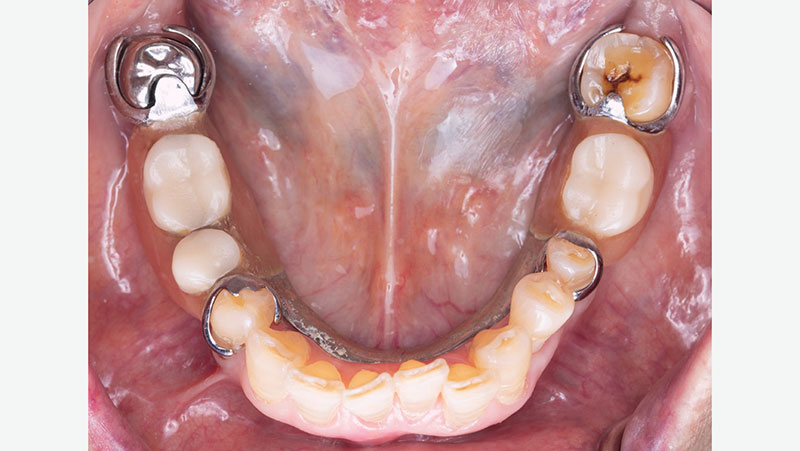

final bruxzir crown

Final BruxZir crown without partial.

partial over final crown

Partial over final BruxZir crown.

Quality Control at Glidewell

As part of the lab’s quality control process, Glidewell supplies a 3D-printed model and a removable pattern of the partial along with the final crown. This is done in order to check the path of insertion, confirm proper seating and verify engagement with the crown. The photos below show an example of a 3D partial duplicate and model that were supplied with a final crown.